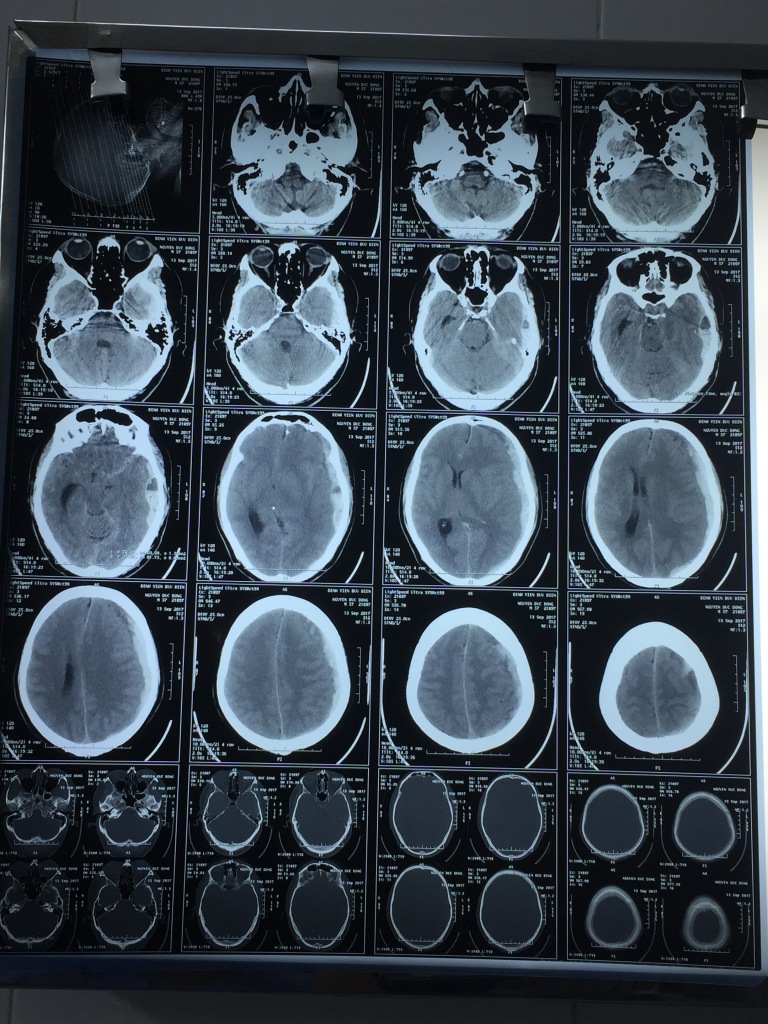

Được chẩn đoán mắc sốt xuất huyết phải nhập viện điều trị, mặc dù được các bác sĩ theo dõi sát sao, điều trị theo đúng phác đồ và được kiểm soát thường xuyên về huyết áp, tuy nhiên sau 2 ngày điều trị nội khoa , tình trạng của bệnh nhân N.Đ.Đ 57 tuổi, ở Khương Trung – Thanh Xuân – Hà Nội vừa có dấu hiệu chuyển biến tốt bỗng đột ngột trở nặng với dấu hiệu: nôn, mất tri giác. Các bác sĩ Khoa Nội đã chẩn đoán nghi ngờ xuất huyết não và chẩn đoán này đã được xác định bằng chụp hình ảnh CT sọ não cấp cứu: có khối máu tụ lớn dưới màng cứng bán cầu bên trái, có phù não và đè đẩy đường giữa nhiều.

Đối với các bệnh nhân có máu tụ dưới màng cứng cấp tính, tri giác giảm nhanh thì tiên lượng bệnh đã rất nặng, hồi sức hết sức khó khăn khi thực hiện phẫu thuật cấp cứu. Ở trường hợp bệnh nhân vừa có tiền sử cao huyết áp, vừa mắc sốt xuất huyết với số lượng tiểu cầu 59.000/mm3 như ông N.Đ.Đ thì việc cầm máu trong phẫu thuật não cấp cứu càng trở nên khó khăn, nguy hiểm gấp bội. Tuy nhiên, nếu không được phẫu thuật cấp cứu kịp thời thì khả năng tử vong của bệnh nhân là không tránh khỏi. Cuộc hội chẩn liên khoa giữa Ban lãnh đạo Bệnh viện với các bác sĩ khoa Hồi sức cấp cứu, khoa Gây mê Hồi sức, chuyên khoa Phẫu thuật Thần kinh (khoa Ngoại tổng hợp và Bệnh viện Bạch Mai) diễn ra nhanh chóng, bệnh nhân được chỉ định vừa truyền tiểu cầu, vừa mổ mổ cấp cứu lấy máu tụ nội sọ.

Với ca phẫu thuật này, theo TS. BS. Hoàng Văn Bách – Trưởng Khoa Gây mê hồi sức – Phẫu thuật não, mạch máu trên BN có giảm nặng về tiểu cầu và các yếu tố đông máu khiến việc cầm máu hết sức khó khăn cho Phẫu thuật viên. Điều này đòi hỏi các bác sĩ phải rất khẩn trương điều chỉnh các rối loạn đông máu ngay từ trước, trong và sau phẫu thuật bằng truyền các yếu tố đông máu như plasma tươi, khối tiểu cầu, tiểu cầu máy... Rất may trong quá trình phẫu thuật người bệnh đã được truyền kịp thời 4 đơn vị tiểu cầu máy, bù đủ yếu tố đông máu và với phẫu thuật viên có trình độ kinh nghiệm cao đã sớm phát hiện và cầm máu một động mạch não giữa đang chảy liên tục, phẫu thuật lấy hết máu tụ dưới màng cứng. Sau hơn 2 giờ phẫu thuật, bước đầu ca mổ được đánh giá thành công, bệnh nhân đã được kiểm soát nguồn chảy máu, giải tỏa chống phù não. Hiện bệnh nhân đang được điều trị hồi sức tích cực tại Khoa Hồi sức cấp cứu.